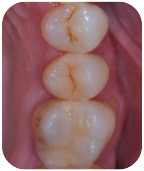

Visto?

E tu credi che questo dente durerà meno di 3 anni? A meno che non ci sia un cataclisma in questi due mesi, ti posso già anticipare di no, perché a novembre questa cura compirà tre annetti e il dente è perfetto sia clinicamente che radiograficamente.

Che non serva averne fatti 1000 per affrontare questa terapia lo dimostra il fatto che questo per me era il primo.

Da allora di riassorbimenti di classe 4 ne ho fatti altri 4 e ho pubblicato la casistica prima sul Journal of Endodontics e poi sul Giornale Italiano di Endodonzia, dopo aver vinto il Premio Lavagnoli al congresso nazionale della SIE presentando i 4 casi suddetti.